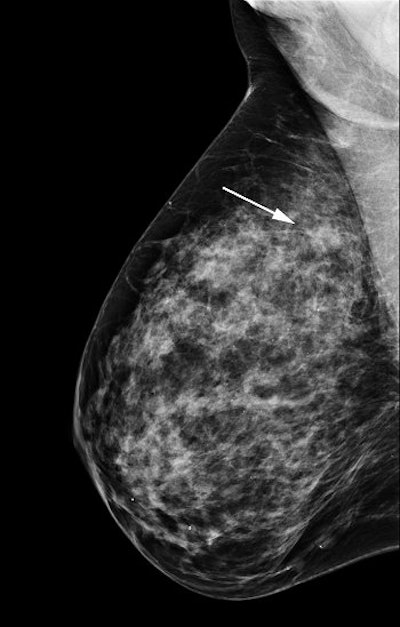

| Tubulolobular adenocarcinoma seen on conventional digital mammogram (left) and in a slice from a tomosynthesis dataset (right). Image courtesy of Hologic. |

The results showed that the ROC curve was superior for DBT compared to FFDM alone for all 12 readers, with the area under the ROC increasing by 0.071 using the BIRADS scale and 0.072 using the probability of malignancy scale. DBT had a sensitivity of 76.2% versus 65.5% for FFDM alone and a specificity of 89.2% versus 84.1%. The mean recall rate was reduced by 42.6%.